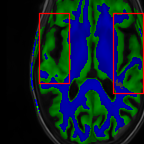

Sparsity LI 2D CNN 3D CNN Ours GT

4 Refer to caption (a) 0.6787/0.7972 Refer to caption (b) 0.8143/0.8776 Refer to caption (c) 0.8190/0.8714 Refer to caption (d) 0.8664/0.9085 Refer to caption (e) GM/WM

Refer to caption (f) 0.6808/0.7161 Refer to caption (g) 0.8103/0.8631 Refer to caption (h) 0.7950/0.8606 Refer to caption (i) 0.8598/0.9115 Refer to caption (j) GM/WM

8 Refer to caption (k) 0.5139/0.7240 Refer to caption (l) 0.6619/0.8224 Refer to caption (m) 0.6878/0.8584 Refer to caption (n) 0.7798/0.8853 Refer to caption (o) GM/WM

Refer to caption (p) 0.5910/0.6947 Refer to caption (q) 0.6516/0.8021 Refer to caption (r) 0.6507/0.8186 Refer to caption (s) 0.7471/0.8540 Refer to caption (t) GM/WM

Figure 6: Visual comparison of gray matter (Green)/white matter (Blue) segmentation over different methods, with respective DICE scores listed under the images.

In Fig. 6, we demonstrate the advantage of the proposed method in brain matter segmentation. It is clear that although 2D and 3D CNN generates visually plausible interpolation as presented in Fig. 5, the brain matters are easily misclassified due to incorrect anatomical structures and blurred details.